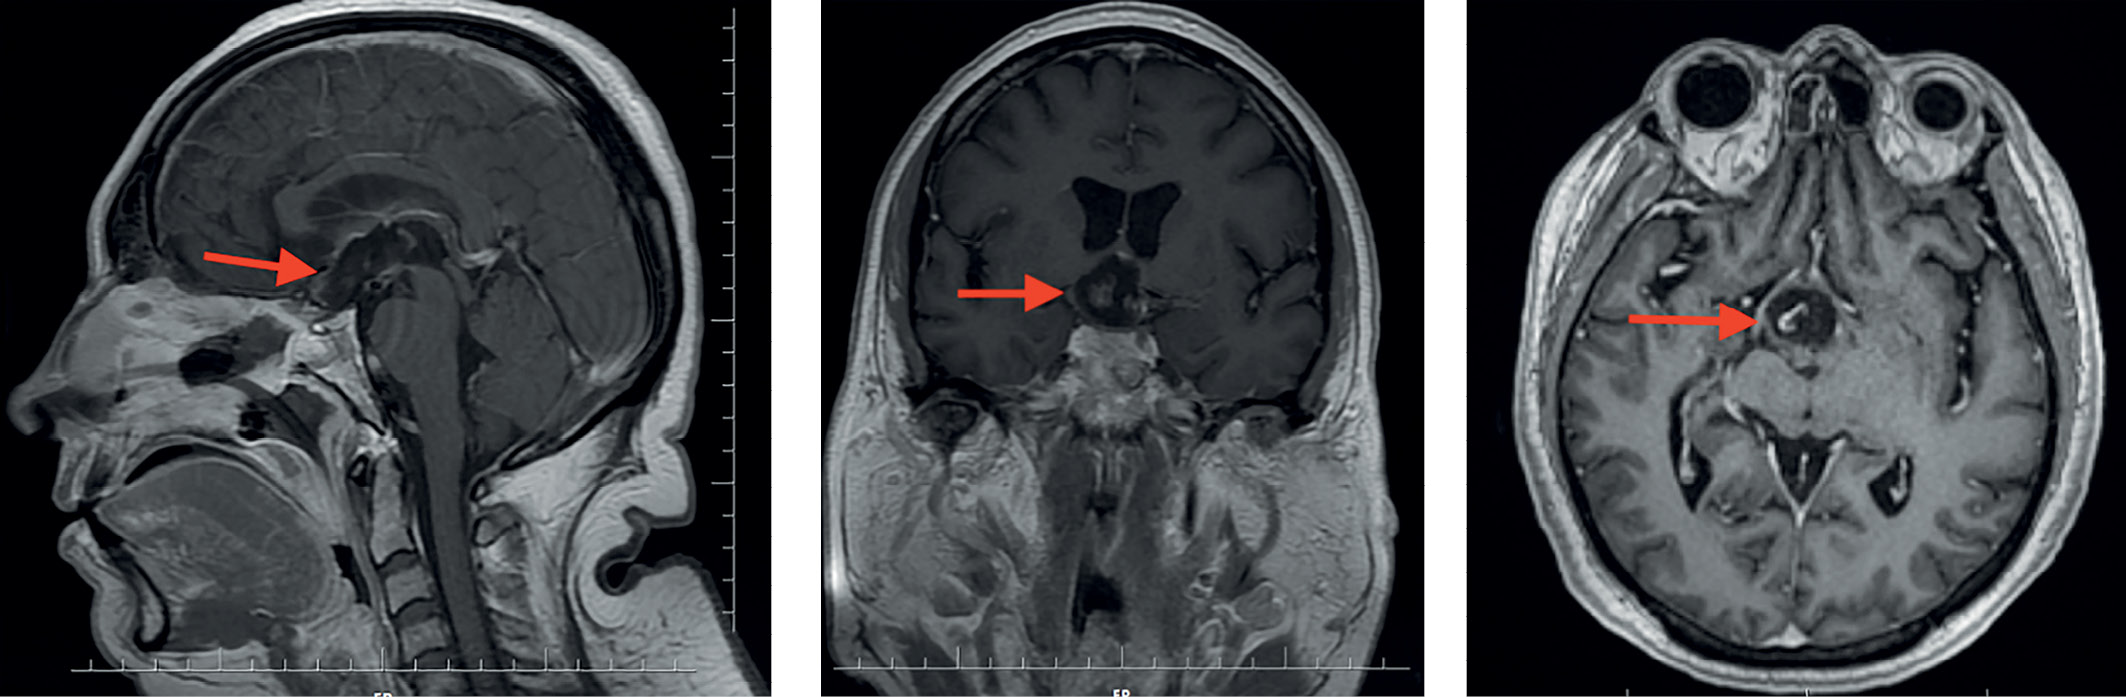

При проведении МРТ головного мозга выявлена солидно-кистозная супраселлярная КФ с интравентрикулярным распространением, вовлечением стебля гипофиза (рис. 1).

Рисунок 1. МРТ пациентки З. до операции. Визуализируется солидно-кистозная супраселлярная краниофарингиома с интравентрикулярным распространением, вовлечением стебля гипофиза (обозначена и указана стрелкой).

Figure 1. MRI of patient Z. before surgery. A solid cystic suprasellar craniopharyngioma with intraventricular extension involving the pituitary stalk is visualized (marked and indicated by an arrow).